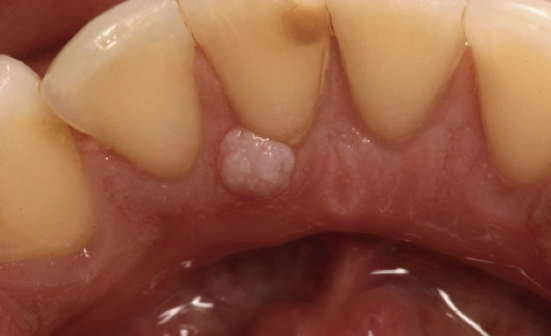

What is the likely Dx?

Fibroma.